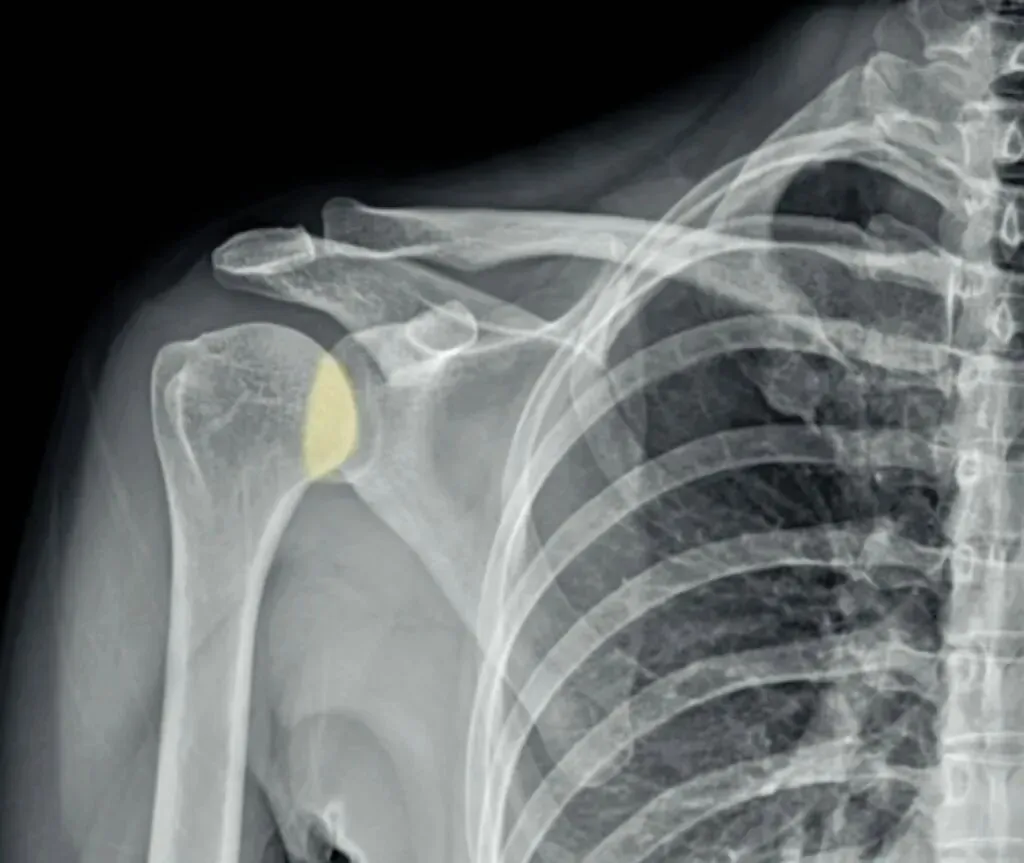

了解完肩关节X线解剖结构后,我们再来看正常的肩关节,肱骨头与关节盂是有部分重叠的,称为半月重叠征,或半月征。

当发生后脱位时,肱骨头与关节盂前缘距离大于等于7毫米,甚至关节盂变为空虚,

表现为关节盂前缘形成类似环的影像,称为环征。